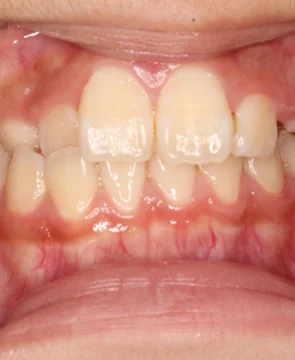

2026/02/24上の前歯が捻じれていることが気になる7歳女児の矯正症例紹介 患者様は上の前歯が捻じれていることを気にされており、矯正検査後叢生Ⅰ級と診断いたしました。 治療前後の比較 矯正術前:正面 矯正術後:正面 矯正術前:右側 矯正術後:右側 矯正術前:左側 矯正術後:左側 矯正術前:上顎 矯正術後:上顎 矯正術前:下顎 矯正術後:下顎 矯正術前:前歯部あおり 矯正術後:前歯部あおり 矯正術前:オーバージェット 矯正術後:オーバージェット 主訴 上の前歯が捻じれていることが気になる 治療期間 ・マウスピース矯正:6カ月 治療費用 660,000円…